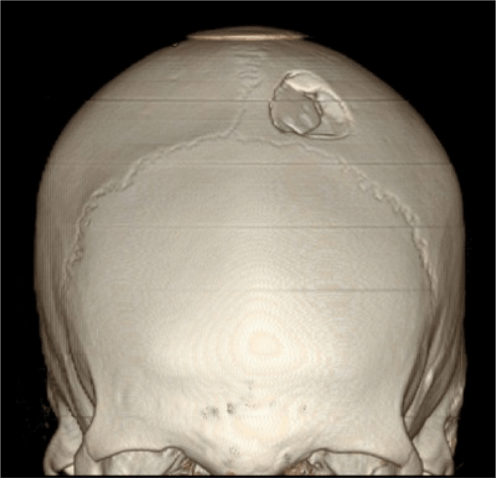

FRACTURAS DE CRÁNEO.

Con ventana de hueso.

Las reconstrucciones 3D-VR aumentan la capacidad diagnóstica de las fracturas desplazadas y no desplazadas.

La presencia de fractura no se correlaciona con la severidad del daño cerebral, sin embargo, la incidencia de hemorragia intracraneal es mayor en pacientes con fractura que en los que no la presentan. Al mismo tiempo, el 25% aprox. de pacientes con daños cerebrales fatales no muestran fractura de cráneo.